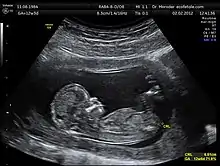

Crown-rump length (CRL) is the measurement of the length of human embryos and fetuses from the top of the head (crown) to the bottom of the buttocks (rump). It is typically determined from ultrasound imagery and can be used to estimate gestational age.

The embryo and fetus float in the amniotic fluid inside the uterus of the mother usually in a curved posture resembling the letter C. The measurement can actually vary slightly if the fetus is temporarily stretching (straightening) its body. The measurement needs to be in the natural state with an unstretched body which is actually C shaped. The measurement of CRL is useful in determining the gestational age (menstrual age starting from the first day of the last menstrual period) and thus the expected date of delivery (EDD). Different babies do grow at different rates and thus the gestational age is an approximation. Recent evidence has indicated that CRL growth (and thus the approximation of gestational age) may be influenced by maternal factors such as age, smoking, and folic acid intake. Early in pregnancy gestational age 8 weeks, it is accurate within about +/- 5 days but later in pregnancy due to different growth rates, the accuracy is less. In that situation, other parameters can be used in addition to CRL. The length of the umbilical cord is approximately equal to the CRL throughout pregnancy.